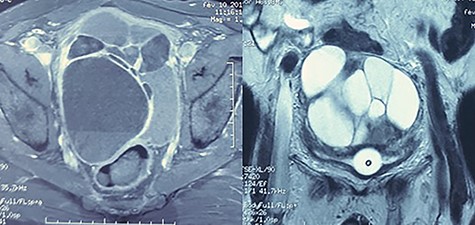

A 59-year-old patient presented at the emergency department with an acute urine retention. As a past medical history, the patient suffered from chronic hypogastric pain with LUTS and constipation over a period of 6 months. The clinical examination revealed a distended bladder that required transurethral bladder catheterization. The digital-rectal examination showed a bulging pelvic mass in the rectum, the prostate has not been palpated. The blood analysis revealed an elevation of creatinine level to 123 μmol/l with hyperleukocytosis. Prostate-specific antigen (PSA) was within normal range and urine culture was negative. Abdominal and pelvic Computed tomography (CT) scan was performed and showed a multilocular heterogeneous cystic mass in the rectovesical and supravesical spaces, measuring 13 × 10 × 9 cm, compressing the bladder and the two ureters with bilateral major upper tract dilation. The cystic mass had many septa of different thickness mildly enhancing after contrast administration (Fig. 1). There were no nodular solid enhancing components or evident signs of lymphadenopathies or metastatic lesions.

CT scan showing pelvic multilocular heterogeneous cystic mass with many septum mildly enhancing after contrast.